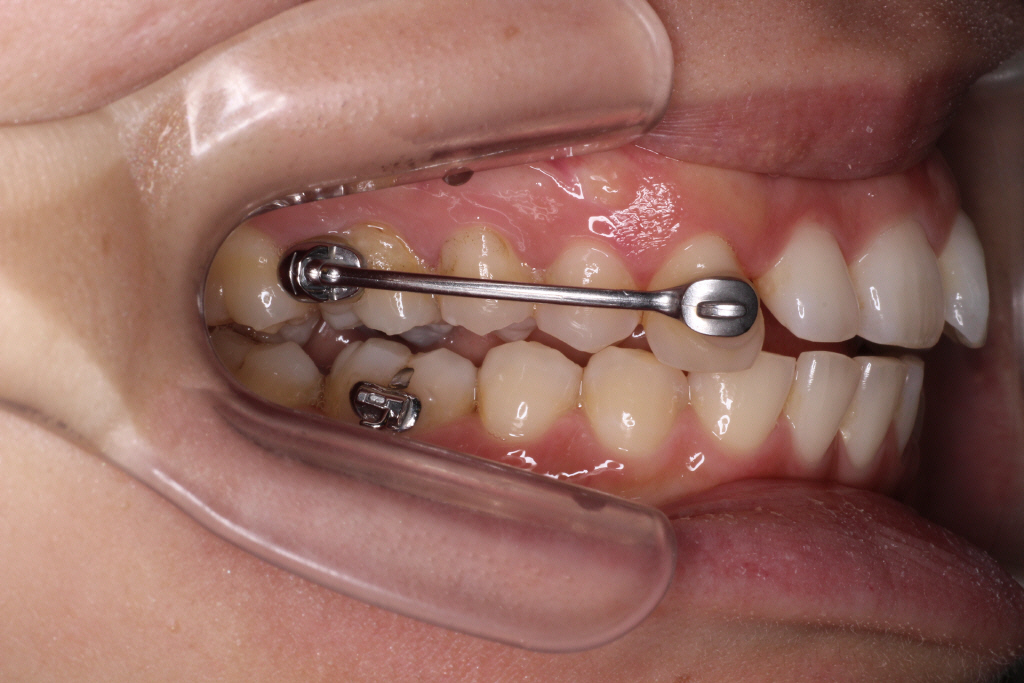

こちらが現在の口腔内写真です。